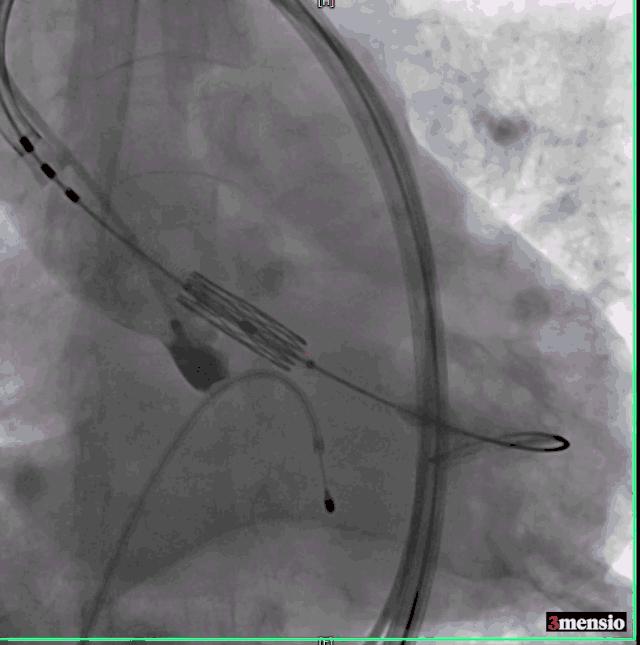

右侧股动脉鞘经Amplatz Super Stiff导丝引导更换为14F 导引鞘,经右侧股动脉用直头导丝带AL2造影管至升主动脉,在直头导丝引导下成功跨越主动脉瓣。

交换Amplatz Super Stiff导丝,再送猪尾导管至左心室,测量左室压力142/6mmHg,升主动脉压力254/58mmHg,跨瓣压差112mmHg,交换Amplatz Super Stiff导丝至左室,撤出猪尾导管,在临时起搏器控制性降压下用20mm球囊扩张主动脉瓣。

球囊扩张